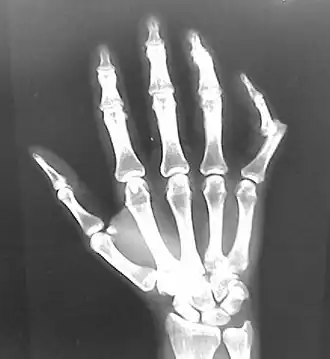

• Wrist

• Overall, injuries to the small bones and ligaments in the wrist are uncommon.[7]

• Lunate dislocations are the most common.[7]